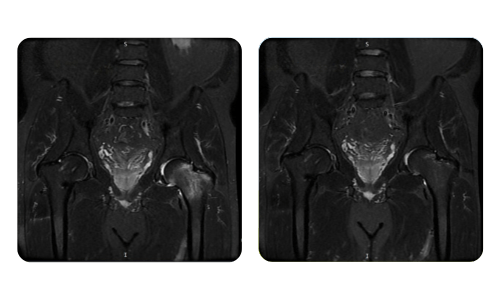

Der Fortschritt unserer Patienten, gemessen vor und nach der hyperbaren Therapie, spiegelt die Effizienz und die positive Wirkung der Behandlung wider. Entdecken Sie dokumentierte Ergebnisse der hyperbaren Therapie in der Klinik Hyperbarium Oradea, basierend auf klinischen Bewertungen und objektiven Daten, die signifikante Verbesserungen bei verschiedenen Erkrankungen belegen.